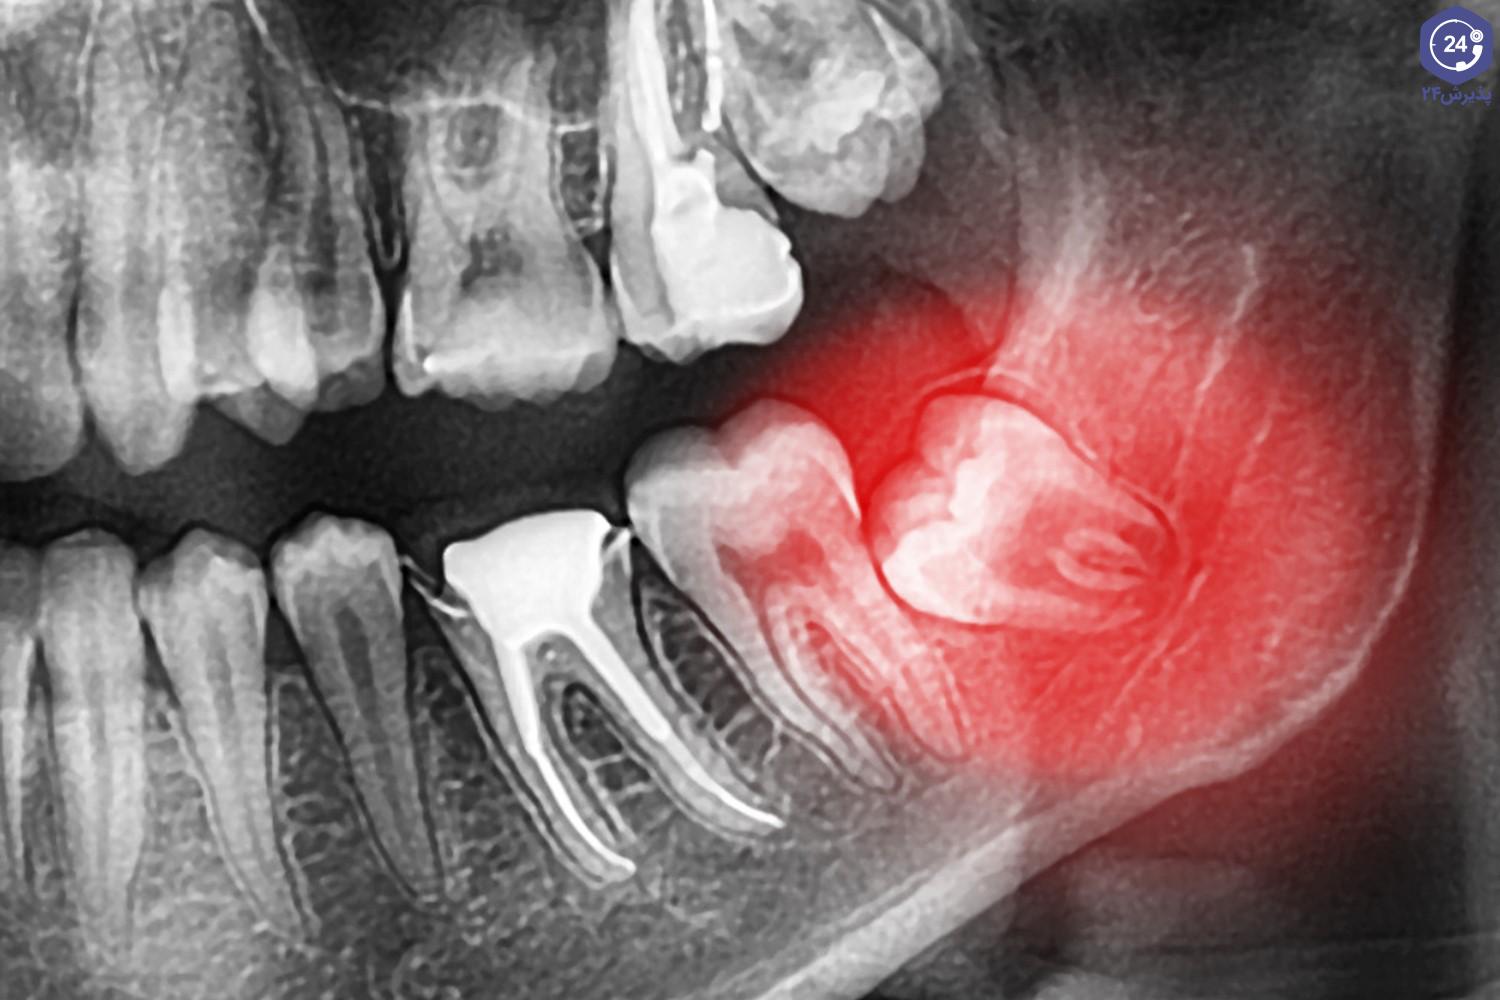

عصب کشی